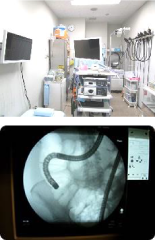

当院では、CTや腹部エコー検査だけでなく、実際にお腹の中を見ることができる大腸内視鏡検査も行っています。

大腸内視鏡検査では、希望される方には鎮痛剤や鎮静剤の注射をして、意識はあっても少しぼーっとした状態(浅い鎮静)で検査を行うことも可能で「苦しい?」「大変?」など心配がある方に「今まで心配で検査ができなかったけど、してみようかな!」と思っていただけるような安心できる体制を整えております。

通常の内視鏡検査では内視鏡の先端から空気を送気して大腸をふくらませて観察します。

そのため、検査後にお腹がはったり気持ち悪くなったりすることがあります。

当院では空気の代わりに二酸化炭素を送気する器具を常備しております。

二酸化炭素は水や体内に吸収されやすいため、検査後のお腹のはりや苦しさを軽減できます。